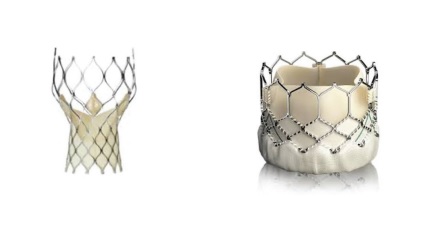

O termo TAVI vem do inglês, Transcatheter Aortic Valve Implantation, ao invés da cirurgia de coração aberto, onde a válvula é removida e substituída, na TAVI significa substituir a válvula nativa sem removê-la, usando um cateter na artéria carregado com uma válvula com stent que é liberada sobre a válvula doente.

A TAVI é uma forma menos invasiva de substituir a válvula para pessoas consideradas de alto risco para cirurgia convencional. Ao invés de cortar o esterno, como na cirurgia de coração aberto, a válvula é guiada através de uma abordagem transcateter. Isso significa que a válvula é entregue em um cateter enquanto comprimida e, em seguida, levada através de uma pequena incisão ou corte no vaso sanguíneo, geralmente na artéria femoral, sendo guiada até o coração. Outras abordagens, como o acesso via um vaso sanguíneo diferente em outro lugar pode ser mais adequado para aguns casos, mas é raro.

Com orientação de fluoroscopia e ecocardiograma (ECO), a nova válvula é colocada sobre a válvula nativa. O objetivo do procedimento é substituir a válvula sem anestesia profunda prolongada e de forma minimamente invasiva, reduzindo o risco do procedimento, as chances de complicações e o tempo de internação.